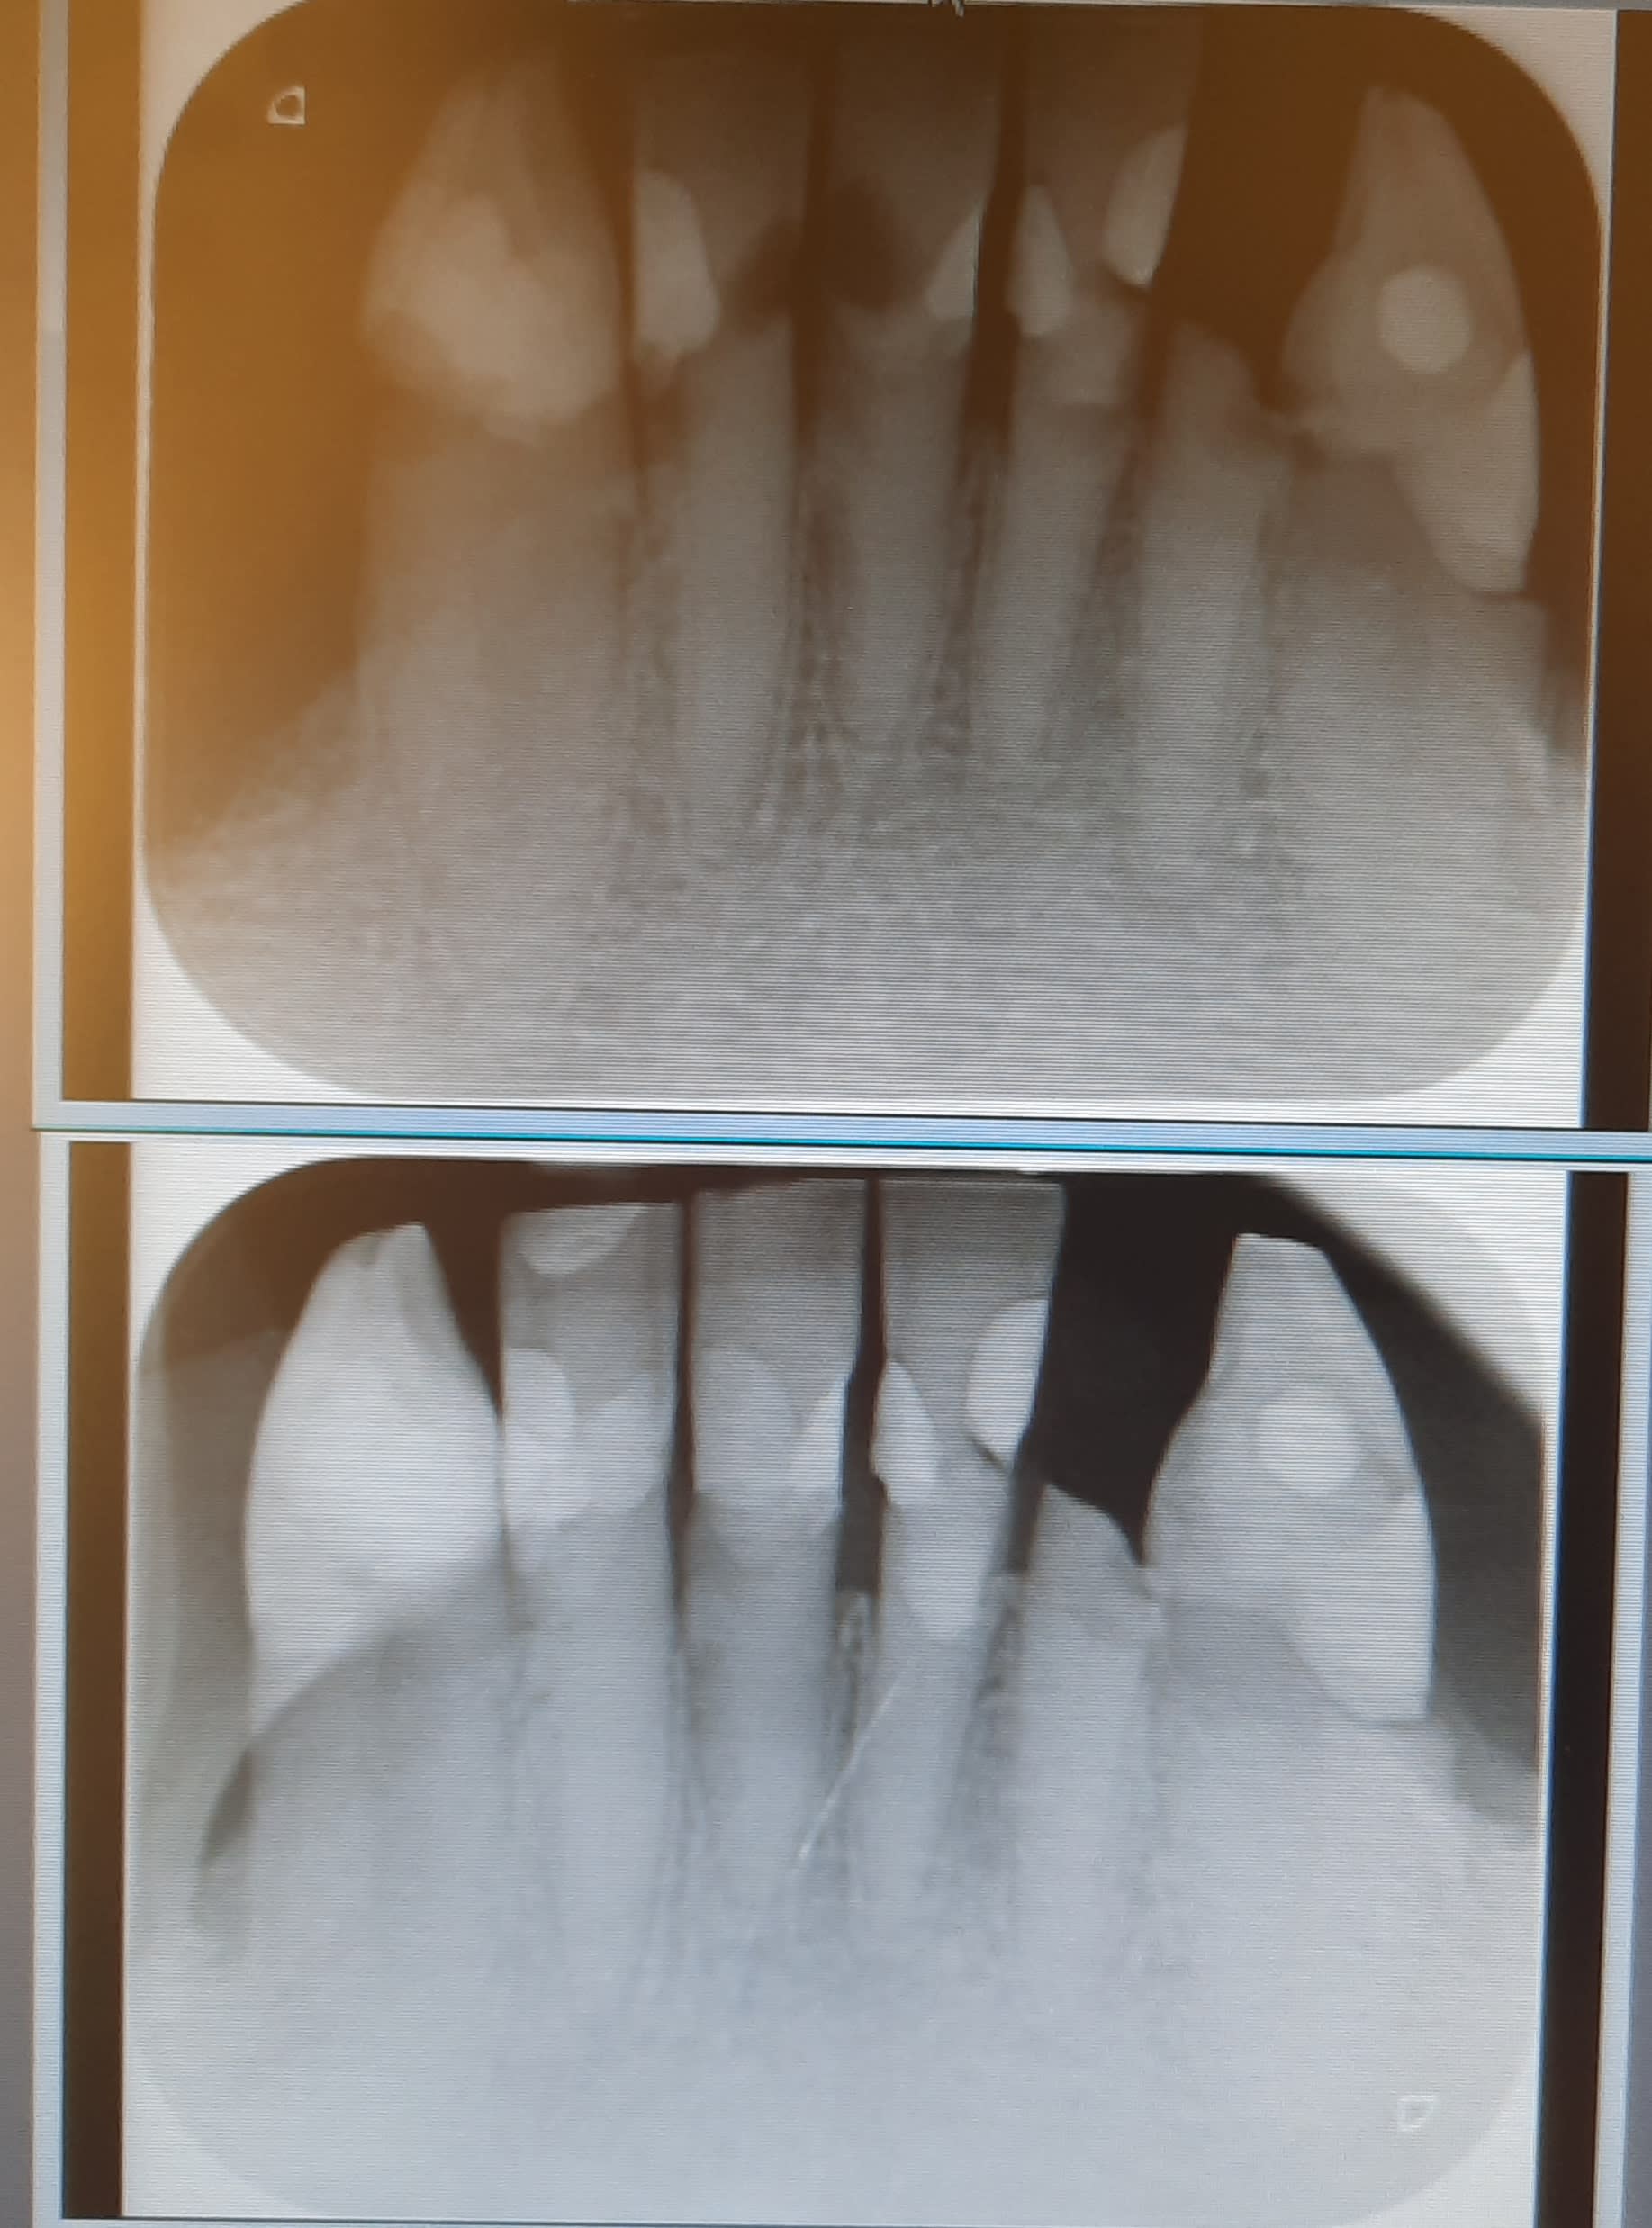

Patiente 80 ans, caries collets circulaires sur toutes les dents restantes, dents fragilisées par l'age et devenues cassantes.

Les molaires ont été extraites suites à reprises de caries sous les anciennes coiffes et devenues irrécupérables.

Il reste de 3 à 3 en haut et en bas, on a pour l'instant 2 ppa résine pour remplacer les postérieures.

En bas je ne sais pas quoi faire.... dents fragilisées que j'ai retapé comme j'ai pu (il reste la 31 à faire).

La 32 s'est fracturée spontanément (tu m'étonnes...).

Je songeais à des coiffes mais les endos me semblent peu réalisables vu la disparition des canaux

Bref coiffer mais sur quoi si je ne peux pas avoir d'ancrage radiculaire?

Bon... après avoir bidouillé l'image j'ai réussi à réduire sa taille....